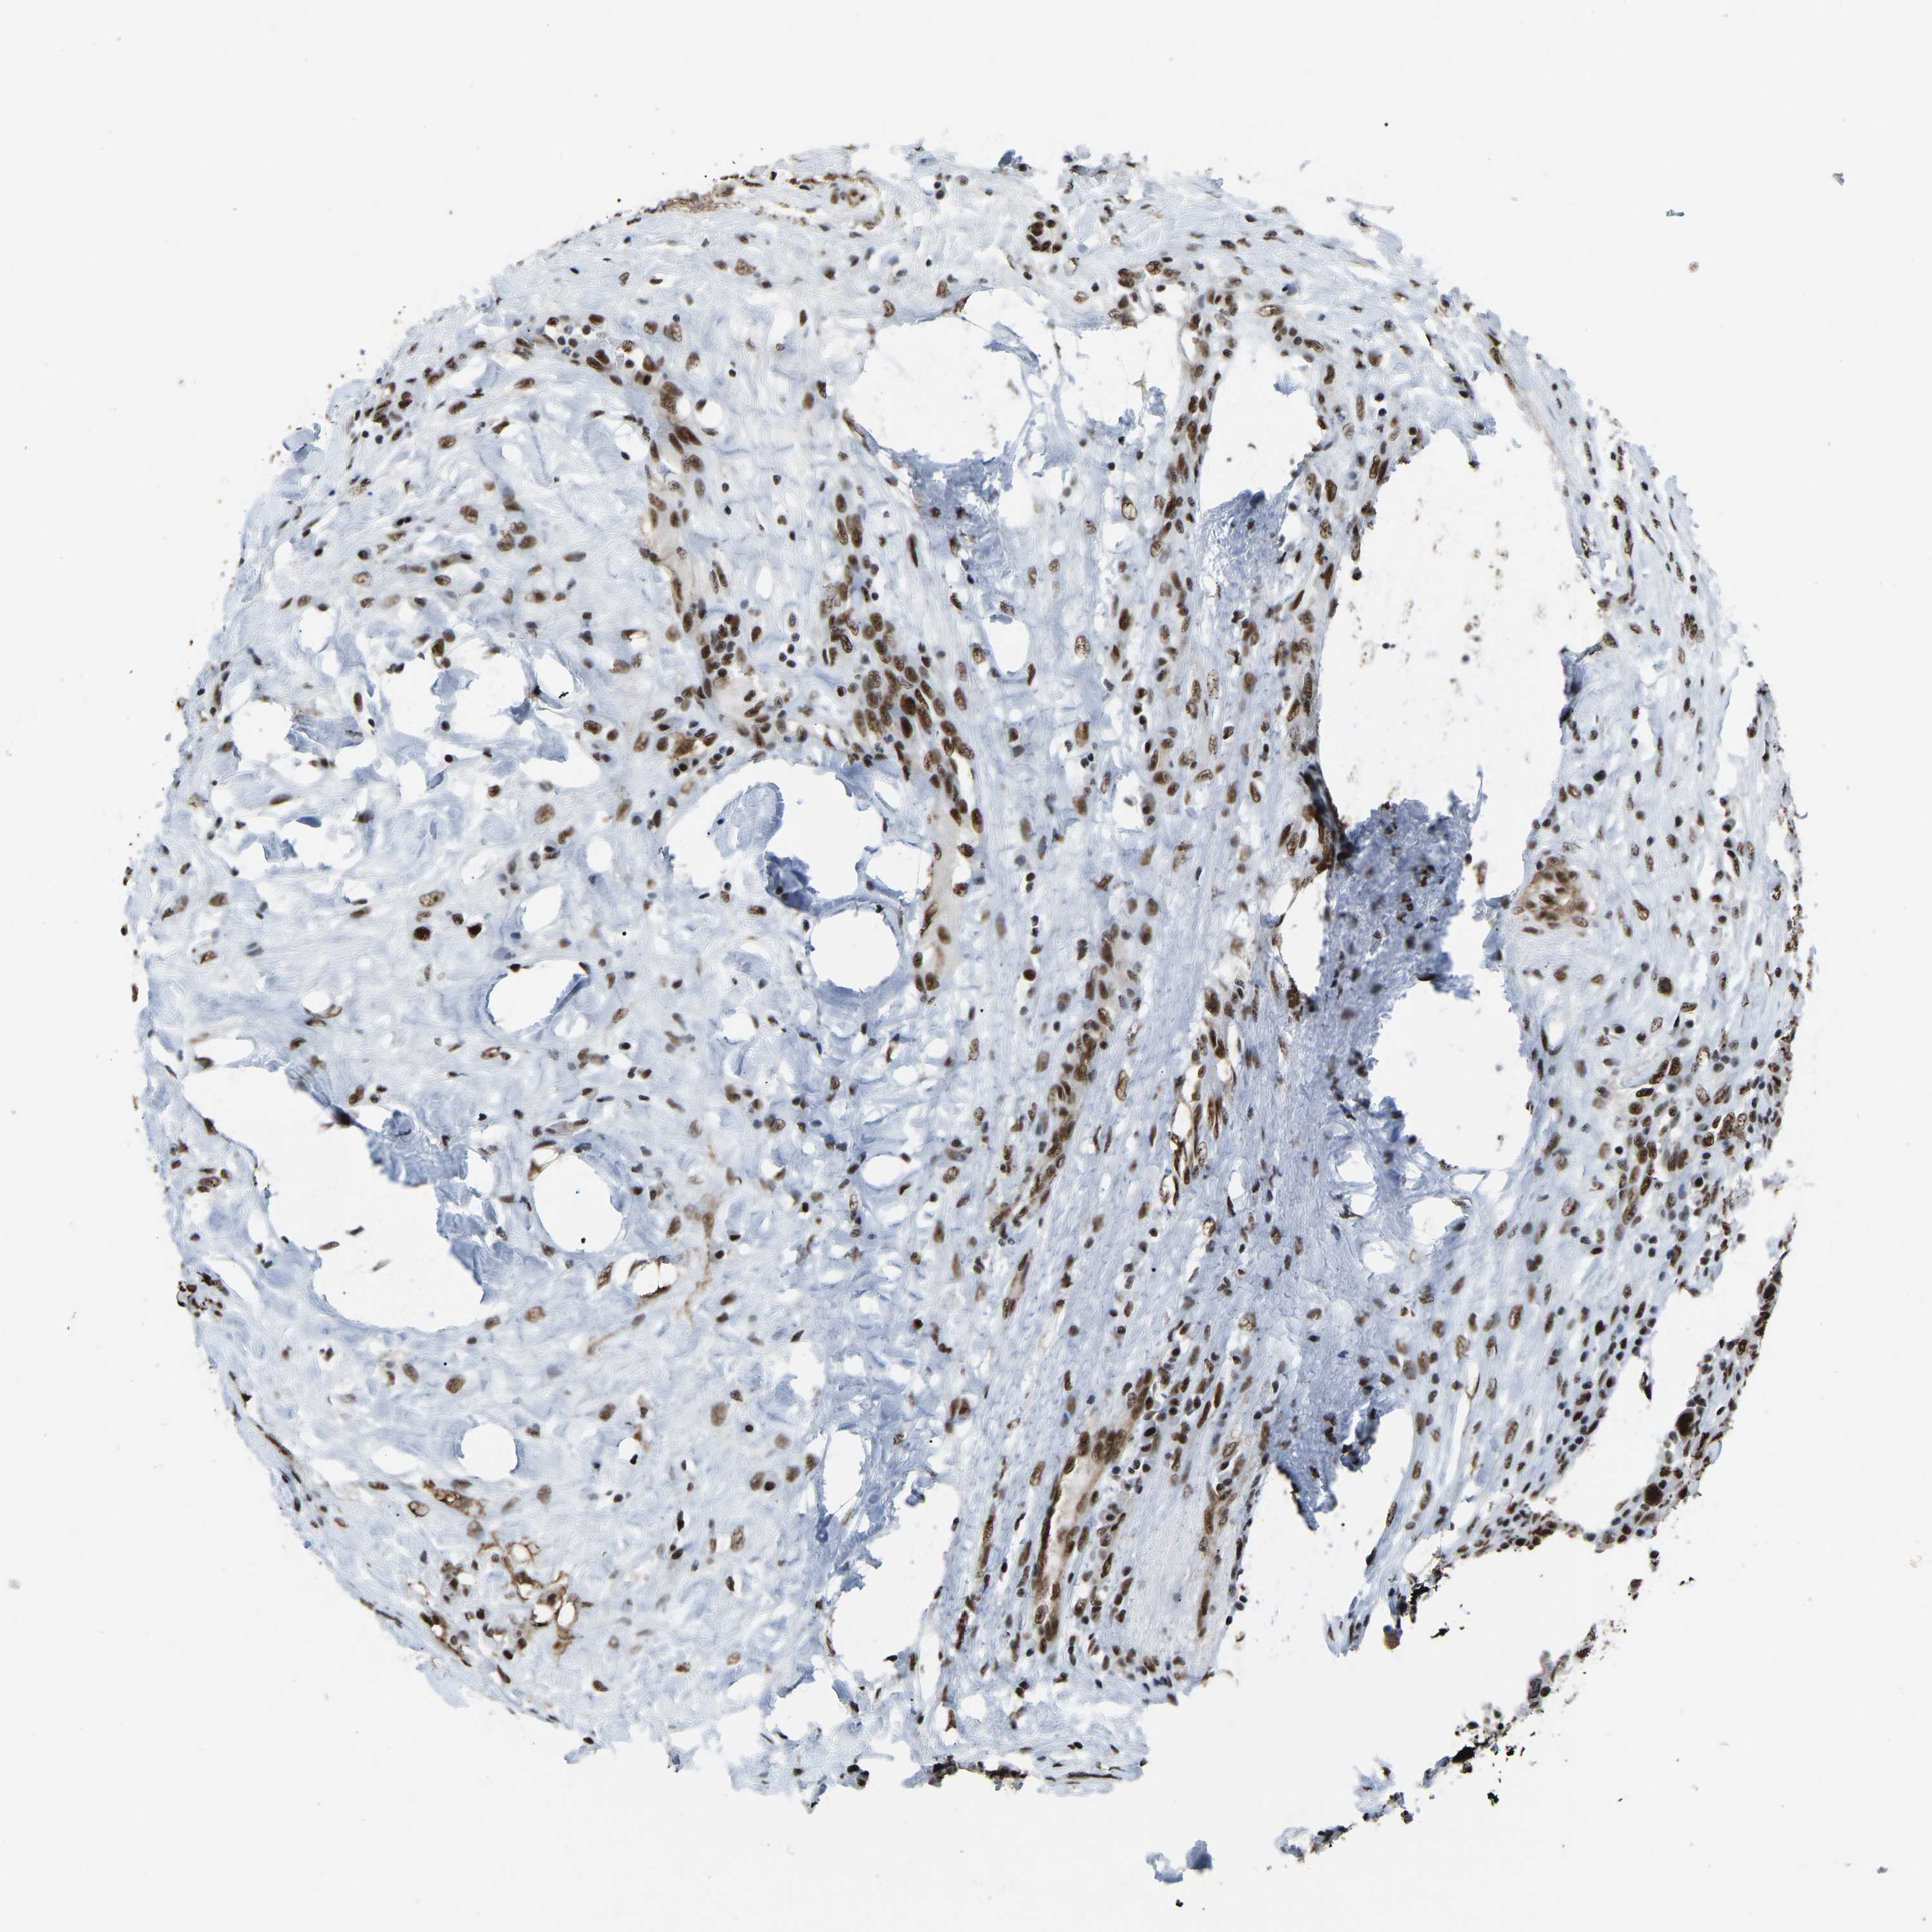

CANCER BREAST CANCER Show tissue menu

BRCA TCGA BRCA VALIDATION PROTEIN EXPRESSION

Breast cancer

Human cancer